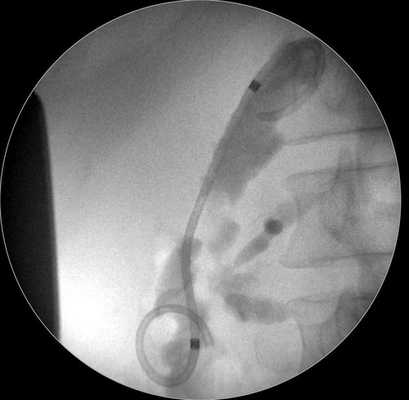

6. Альтернативный метод дренирования состоит в установке по металлическому проводнику, помещенному в полость кисты, наружного назобилиарного катетера, конец которого имеет форму pig-tail (рис. 5). Рис. 5. Наружное эндоскопическое дренирование с использованием назобилиарного катетера, конец которого имеет форму pig-tail (случай 2).

Случай 2. Мальчик в возрасте 15 лет поступил в приемный покой ИМДКБ с жалобами на боли в околопупочной области и рвоту. При разговоре с пациентом стало известно, что около 1 мес назад он совершил падение с высоты при игре со сверстниками. За медицинской помощью не обращался. Исследование крови при поступлении выявило подъем в крови концентрации амилазы до 1397 Ед/л, липазы до 728 Ед/л, концентрации амилазы мочи — до 17 735 Ед/л. Ультразвуковое сканирование органов брюшной полости обнаружило многокамерную псевдокисту в поджелудочной железе на границе хвоста и тела. Магнитно-резонансная томография установила, что в проекции тела и хвоста поджелудочной железы располагается кистозное образование размером 6—8 см с наличием перегородок и гиперэхогенной капсулой толщиной 2 мм. Под общей внутривенной анестезией в желудок установлен эхоэндоскоп. В точке, расположенной на задней стенке желудка и наиболее соприкасающейся со стенкой ППК, произведена пункция кисты с использованием цистотома MTW. При аспирации получено густое содержимое коричневого цвета. Попытка установки стента MTW не увенчалась успехом из-за спадения кисты в момент ее опорожнения, что привело к деформации устройства. В полость ППК установлен металлический проводник, по которому проведен назобилиарный наружный катетер. Конец катетера имеет завиток по типу pig-tail, который надежно фиксируется путем затягивания петли. Дренажная трубка была заведена в полость кисты на глубину около 10 см до исчезновения отверстий. Назобилиарный катетер был выведен через носовой ход и фиксирован к крылу носа. Течение послеоперационного периода гладкое. Объем отделяемого из кисты в 1-е сутки после операции составил 70 мл. Пациент находился в госпитале на протяжении 10 дней. Болевой синдром полностью исчез. Ультразвуковое сканирование обнаружило полное спадение кисты. К моменту выписки объем отделяемого из кисты уменьшился до 10 мл в сутки. Уровень амилазы крови составил 432 Ед/л, липазы — 60 Ед/л, амилазы мочи — 2120 Ед/л. В ходе амбулаторного наблюдения через 30 дней после операции ультразвуковое исследование показало, что выделение патологического содержимого из кисты прекратилось, признаки деформации поджелудочной железы отсутствуют. Биохимический анализ показал значительное снижение концентрации амилазы в крови до 130 мкмоль/л и до 145 Ед/л в моче. Катетер был удален. Дальнейшее наблюдение за больным в течение 18 мес показало нормализацию концентрации в крови амилазы и отсутствие признаков рецидива.